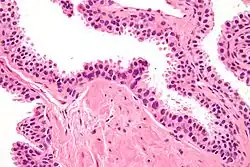

| Micrograph showing high-grade prostatic intraepithelial neoplasia. H&E stain. | |

Microscopically, PIN is a collection of irregular, atypical epithelial cells. The architecture of the glands and ducts remains normal. The epithelial cells proliferate and crowding results in a pseudo-multilayer appearance. They remain fully contained within a prostate acinus (the berry-shaped termination of a gland, where the secretion is produced) or duct. The latter can be demonstrated with special staining techniques (immunohistochemistry for cytokeratins) to identify the basal cells forming the supporting layer of the acinus. In prostate cancer, the abnormal cells spread beyond the boundaries of the acinus and form clusters without basal cells. In HGPIN, the basal cell layer is disrupted but present. PIN is primarily found in the peripheral zone of the prostate (75-80%), rarely in the transition zone (10-15%) and very rarely in the central zone (5%), a distribution that parallels the zonal distribution for prostate carcinoma.[7]